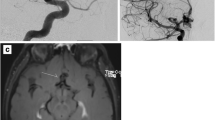

Inflammation was present to some degree in all our samples (Fig. 1). Strong inflammation (grade 2 or 3) was present in 87.1% of the samples. Infiltration of inflammatory cells into brain parenchyma and bAVM vessel walls was clearly observed both in ruptured and unruptured bAVMs. Multiple types of inflammatory cells were present, including neutrophils, eosinophils, macrophages, and lymphocytes. Inflammation in bAVM tissue sample did not associate with any of the clinical variables. There was no association between prior clinically diagnosed rupture and inflammatory cell infiltration (median inflammation score 2, range 1–3 in both unruptured and ruptured bAVMs, p = 0.442). Of the bAVMs with strong inflammation, 55.4% (41/74, p = 0.106) were ruptured. A summary of patient demographics and of the clinical presentation is given in Table 1.

Hematoxylin and eosin staining on sections from unruptured and ruptured bAVM tissues. Strong inflammation was present in parenchyma both unruptured (a) and ruptured (b) bAVMs. In addition to inflammation of the brain parenchyme adjacent to the bAVM nidus, also, perivascular inflammation was found both in unruptured (c) and ruptured (d) bAVMs. Neutrophil adhesion and infiltration of the bAVM vessels was seen in both unruptured (e) and ruptured (f) bAVMs